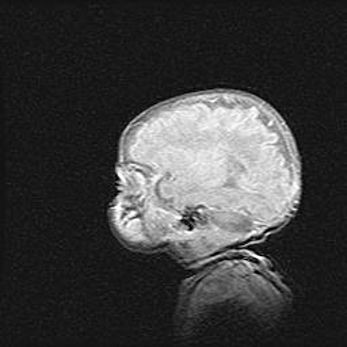

Церебральная ишемия II.

Возраст: 7 дней

Вес: 3350 г

Пол: женский

Окружность головы: 35 см

Срок гестации: 39 недель

Ишемия головного мозга – это состояние, которое развивается в ответ на кислородное голодание вследствие недостаточного мозгового кровообращения. У новорожденных она является следствием дефицита кислорода, что ведет к метаболическим расстройствам различной степени тяжести в тканях головного мозга, в том числе к развитию коагуляционных некрозов и гибели нейронов.